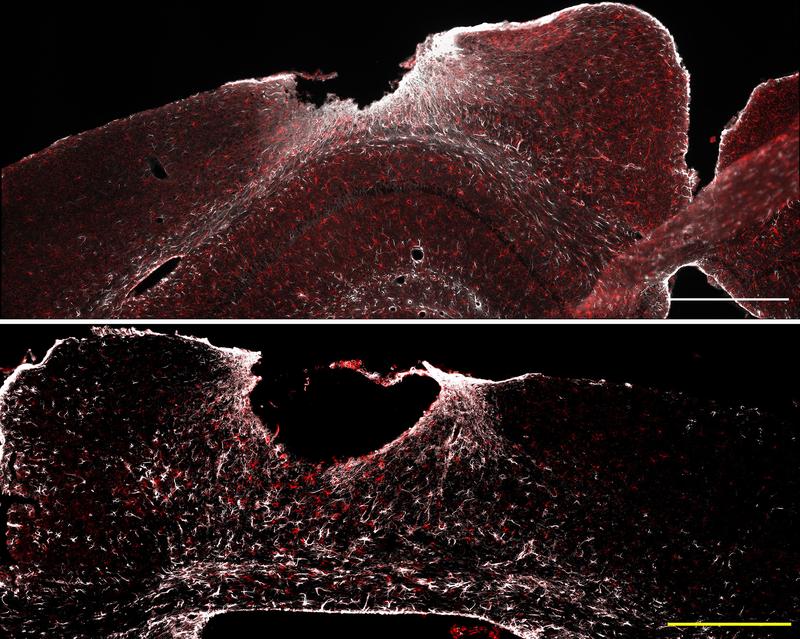

Die sternförmigen Gliazellen spielen außerdem eine Schlüsselrolle bei der Vernarbung von verletztem Hirngewebe. „An der geschädigten Stelle umschließen Astrozyten den Wundkern. So begrenzen sie weitere neurodegenerative Prozesse und unterstützen die Heilung“, erläutert Professorin Leda Dimou. Die Leiterin der Abteilung Molekulare und Translationale Neurowissenschaften an der Klinik für Neurologie war an der Studie federführend mitbeteiligt. In unmittelbarer Nähe der Verletzung fanden die Forschenden eine auffällige Genexpressionssignatur – ein Hinweis auf eine besonders hohe Aktivität von NF-κB in Astrozyten. Um den Einfluss dieses Genschalters genauer zu untersuchen, arbeiteten die Forschenden mit Mausmodellen. In diesen war NF-κB in Astrozyten entweder dauerhaft aktiviert oder stark gehemmt. Das Team wollte wissen: Verbessert oder verschlechtert sich dadurch die Heilung nach einer traumatischen Hirnverletzung?

Das Ergebnis fiel eindeutig aus: War NF-κB dauerhaft aktiv, reagierte das Immunsystem schneller und stärker auf die Verletzung. Diese überschießende Neuroimmunantwort löste Entzündungsprozesse aus und störte sowohl Wundheilung als auch Narbenbildung.

„In den Wundbereich wanderten plötzlich auch bestimmte Immunzellen wie dendritische Zellen ein. Dadurch konnte sich kein stabiles Narbengewebe bilden, was schließlich zu neurologischen Defiziten führte“, berichten die Erstautorinnen der Studie, Tabea M. Hein und Ester Nespoli. Erstaunlich: Ganz ähnliche Prozesse zeigen sich im alternden Gehirn. Wurde NF-κB in Astrozyten dagegen gehemmt, waren einzelne positive Effekte zu beobachten: So verbesserten sich die antioxidative Abwehr und die Funktion der Mitochondrien. „Diese Veränderungen reichten jedoch nicht aus, um den Heilungsprozess insgesamt deutlich zu verbessern“, erklären die Forschenden.

Auch wenn noch Fragen offen sind, liefern die Ergebnisse wichtige Hinweise für neue Therapieansätze. Besonders auffällig ist die Rolle bestimmter Glykoproteine im Knochenstoffwechsel. So wird das für Gewebebildung und Wundheilung wichtige Osteopontin (OPN) bei übermäßiger NF-κB-Aktivierung im Verletzungsbereich nur unzureichend gebildet, was die Heilung beeinträchtigt. Im Gegensatz dazu wird verstärkt Lipocalin-2 (LCN2) produziert. Dieses Protein kann schädliche neuroentzündliche Prozesse fördern und etwa die Blut-Hirn-Schranke beeinträchtigen. „Hier könnten sich neue Therapieansätze ergeben, indem die Spiegel dieser beiden Faktoren gezielt reguliert werden“, sagt Bernd Baumann.